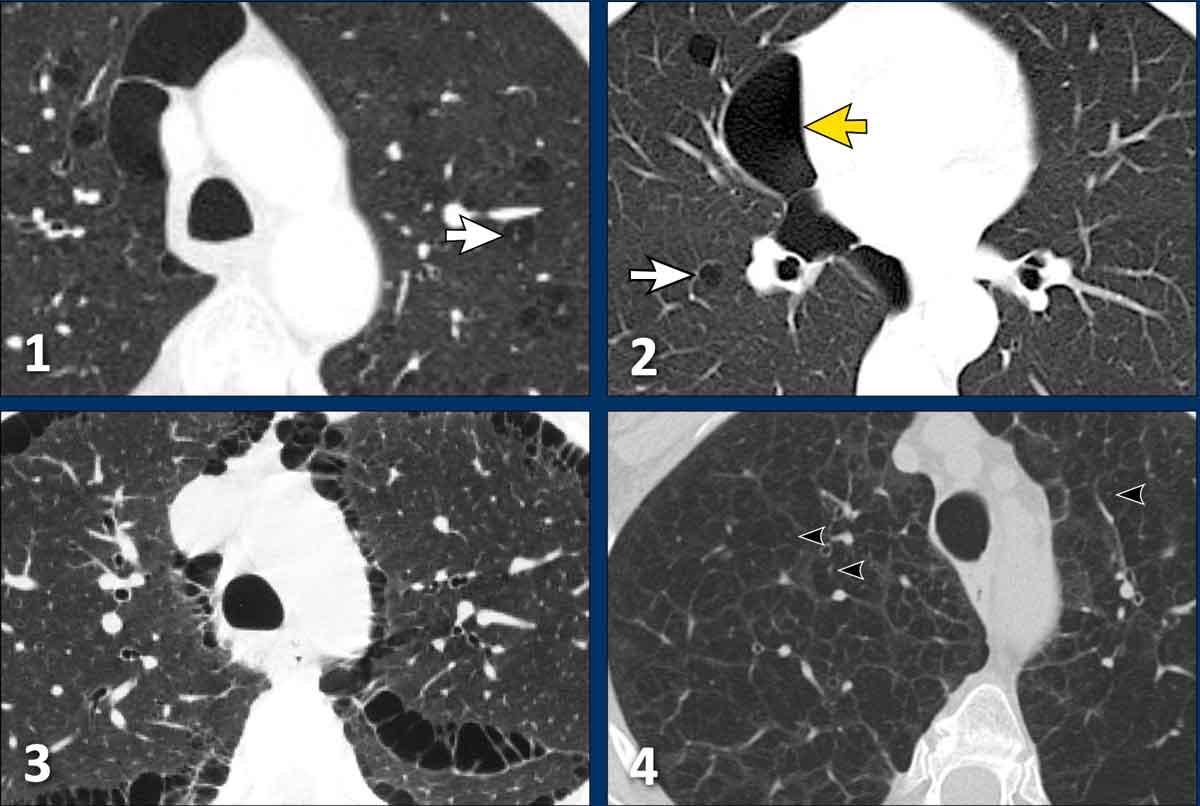

Hình ảnh

- Các nang đơn thuần trong nền kính mờ lan tỏa.

- Các nang đơn thuần trong LIP. Đôi khi có thể thấy các lõm mạch máu hoặc vách ngăn. Các vách ngăn này có thể bắt chước hình ảnh chấm trung tâm như trong khí phế thũng trung tiểu thùy.

- Các nang đơn thuần trong vùng kính mờ.

- Các nang đơn thuần kèm lưới hóa mờ nhạt và kính mờ.

Các hình ảnh này của một nam bệnh nhân 55 tuổi có triệu chứng khó thở.

Bệnh nhân có tiền sử bệnh mô liên kết hỗn hợp (MCTD) và không hút thuốc lá.

Hãy phân tích hình ảnh.

Dấu hiệu đặc trưng nhất là gì?

Chẩn đoán có khả năng nhất là gì?

Nhận xét

Dấu hiệu đặc trưng nhất là sự kết hợp giữa các nang và kính mờ.

Bàn luận

Chẩn đoán có khả năng nhất dựa trên các dấu hiệu hình ảnh là LIP.

Tiền sử bệnh mô liên kết hỗn hợp cũng là yếu tố gợi ý quan trọng.

Chẩn đoán viêm phổi kẽ bong vảy (DIP) ít có khả năng, do bệnh nhân không hút thuốc lá và trong DIP tất cả các nang phải nằm trong vùng kính mờ. Trong trường hợp này, một trong các nang rõ ràng nằm trong vùng nhu mô phổi bình thường (mũi tên).

Khí phế thũng

Một số ví dụ về khí phế thũng được đưa vào đây vì khí phế thũng đôi khi có thể mô phỏng hình ảnh bệnh phổi dạng nang.

- Khí phế thũng trung tiểu thùy và cạnh vách. Lưu ý sự tương đồng với hình 2, nhưng sự phân bố khác nhau (vùng trên so với vùng dưới) và sự hiện diện của các chấm trung tâm (mũi tên trắng) giúp phân biệt.

- Đây không phải khí phế thũng mà là trường hợp hội chứng Birt-Hogg-Dubé với các nang đơn thuần trong nhu mô phổi và các nang cạnh màng phổi.

- Khí phế thũng cạnh vách.

- Khí phế thũng trung tiểu thùy với dấu hiệu chấm trung tâm (đầu mũi tên đen). Lưu ý sự khác biệt tinh tế so với LCH giai đoạn tiến triển (xem Hình 2 ở phần LCH phía trên), biểu hiện các vách ngăn hoặc thành nang rõ hơn.